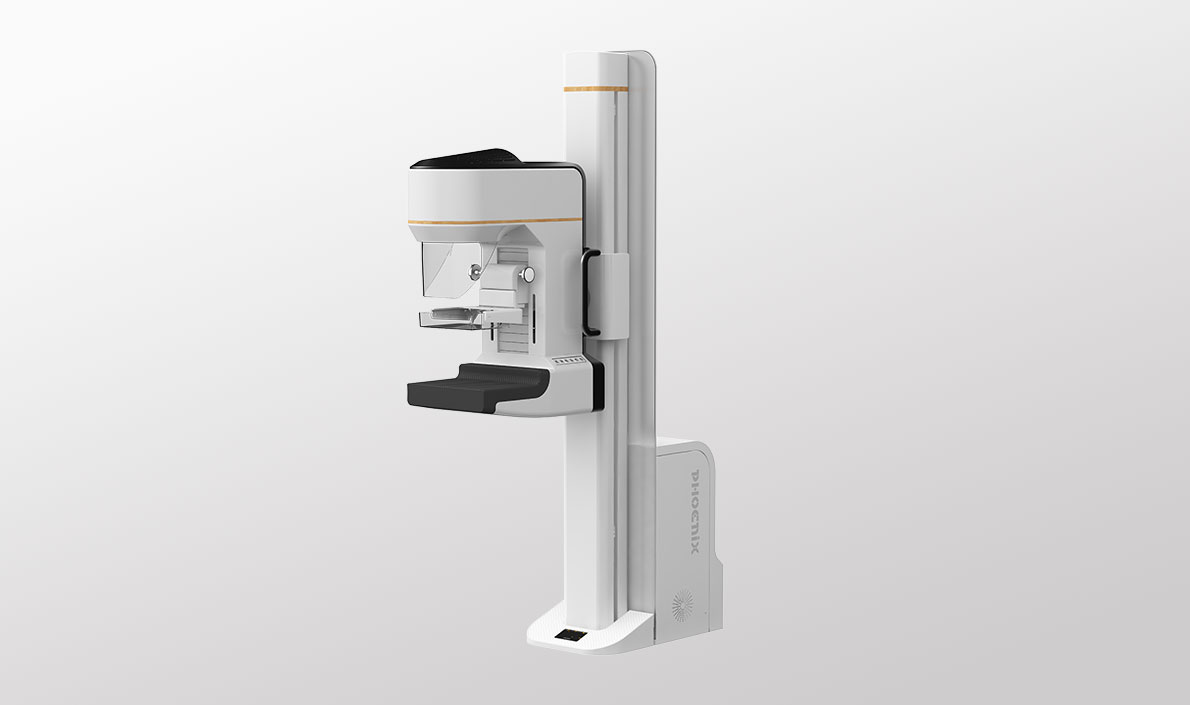

全乳覆盖高效检查

稳定灵活,操控随心

角度记忆功能,快速精准摆位 C型臂270度全角度覆盖 非等中心旋转 一键快速换位

模块化配置